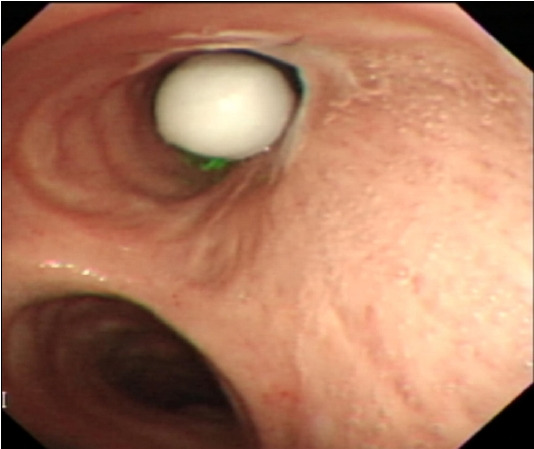

Bifurcated Lumen Observed on Capsule Endoscopy.

胶囊内窥镜观察到分岔管腔